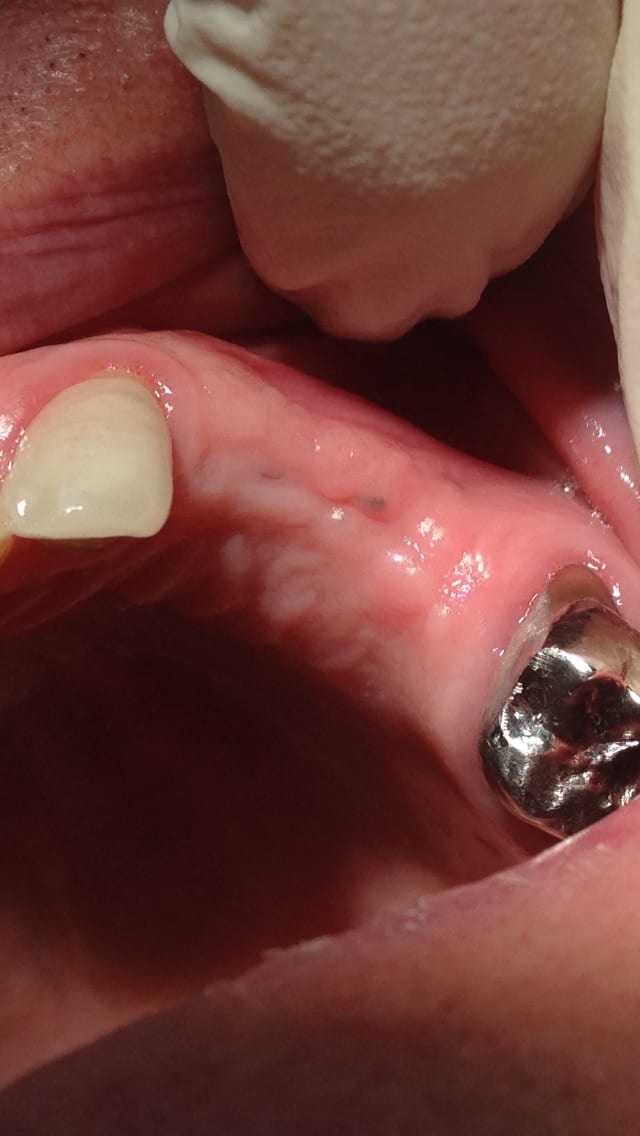

Cicatrisation à une semaine après mon cas , quasi pas de douleur pour le patient :

https://www.dropbox.com/s/1vc1v2sgawc8tnp/IMG_0616.JPG?dl=0

porte t'il un provisoire ?

Surtout pas